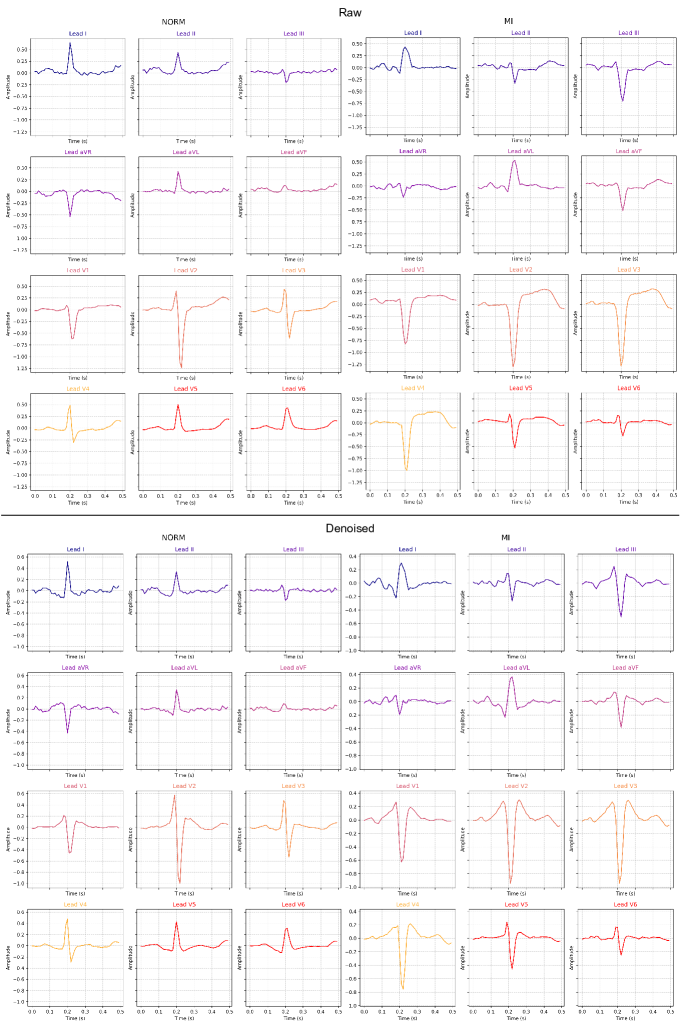

The effect of denoising on one beat is demonstrated for two random samples in Figure C.3. Moreover, in Figure C.4, we can also observe how the signal in each lead changes discretely for the samples.